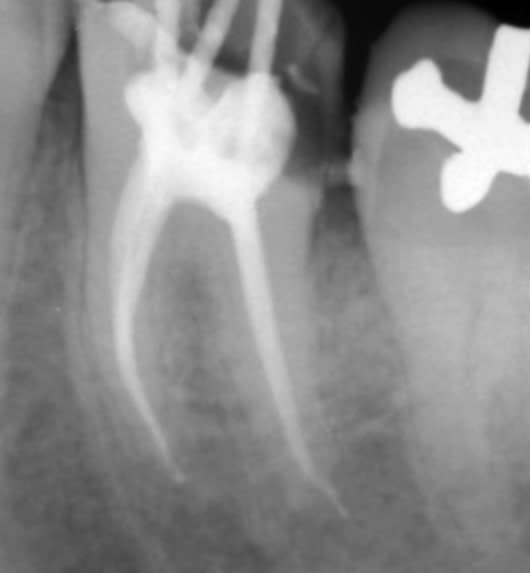

On fait quoi?

On fait quoi lu1sts - Eugenol

Symptomatique?

je te le dis dans 20 min ;-) la patiente arrive.

asympto, je surveille tous les 6 mois. Un jour faudra peut être faire quelque chose.

La prov est scellée au polycarboxylates, donc étanche.

Je me connais, si elle se descellait, je tenterais une CR avec un moignon compo probablement.

L'implant c'est la facilité...

On sent bien la French touch, en plus c'était pas du low-coast!!

Peut être que le confrère qui a mis le tenon, n'était pas le même que celui qui a posé le screw post ?

Bien vu. Le tenon, c'est pas le souci, tu supprimes le surplomb en Ml, ça redresse l'axe et ... et quoi au fait?-)

Le screw c'est chiant, asympto depuis 15 à 20 ans effectivement.

Perso, je surveille l'espace inter radiculaire et j'attends que ça se descelle... qu'il se passe quelque chose.

je pense reconnaître la même philosophie de soins sur la 45, j'espère pas y toucher:-))

Si ya pas de perfo en regard du screw post je m'en coupe une.

Nan pas fait, c'est asympto et ça changerait rien de faire un 3D (voir les recommandations, la prescription d'un 3D doit apporter un bénéfice, là y a pas)... on le saura le jour le l'autopsie:-)

Personne est pour déposer le screw, bourrer au MTA, rte, IC, CR:-))